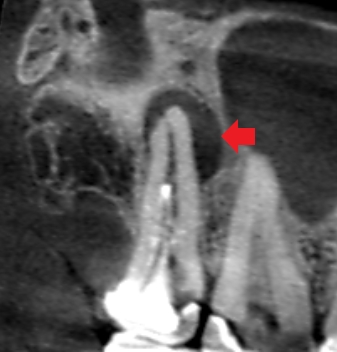

精密根管治療6ヶ月後の経過観察時の上顎第二大臼歯の冠状断のCT画像です。矢印の先に見えていた長い膿の影が消失しています。

精密根管治療により膿が改善したので、根尖孔外感染ではありませんでした。手術が難しいケースだったので、抜歯を免れることができました。